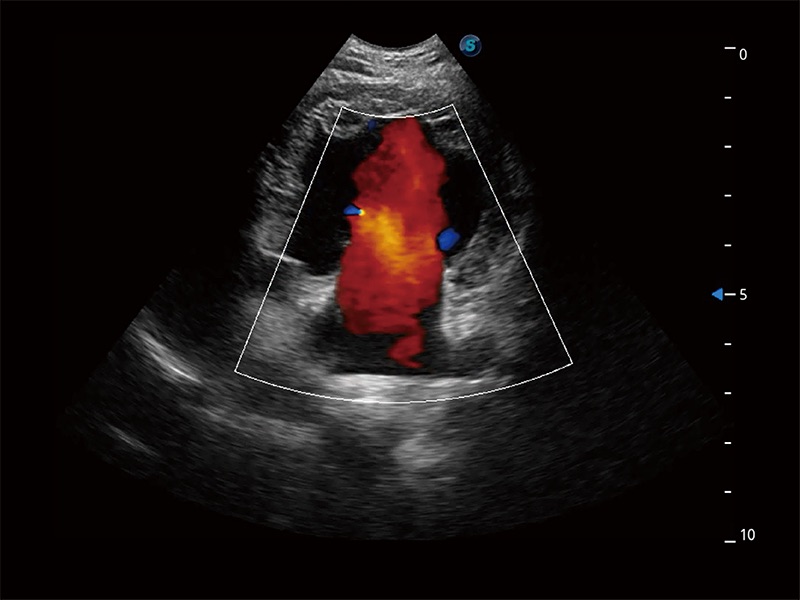

优异的基础图像

ProPet 80 全新的动物超声智能软件和丰富的探头群,为动物医生提供了高清晰度和精细分辨率的图像,无论在宠物、马科、畜牧还是实验室动物等应用中都可以轻松应对,为您的日常工作带来满意的体验。

(犬)胎儿主动脉弓立体血流

(犬)二腔心血流